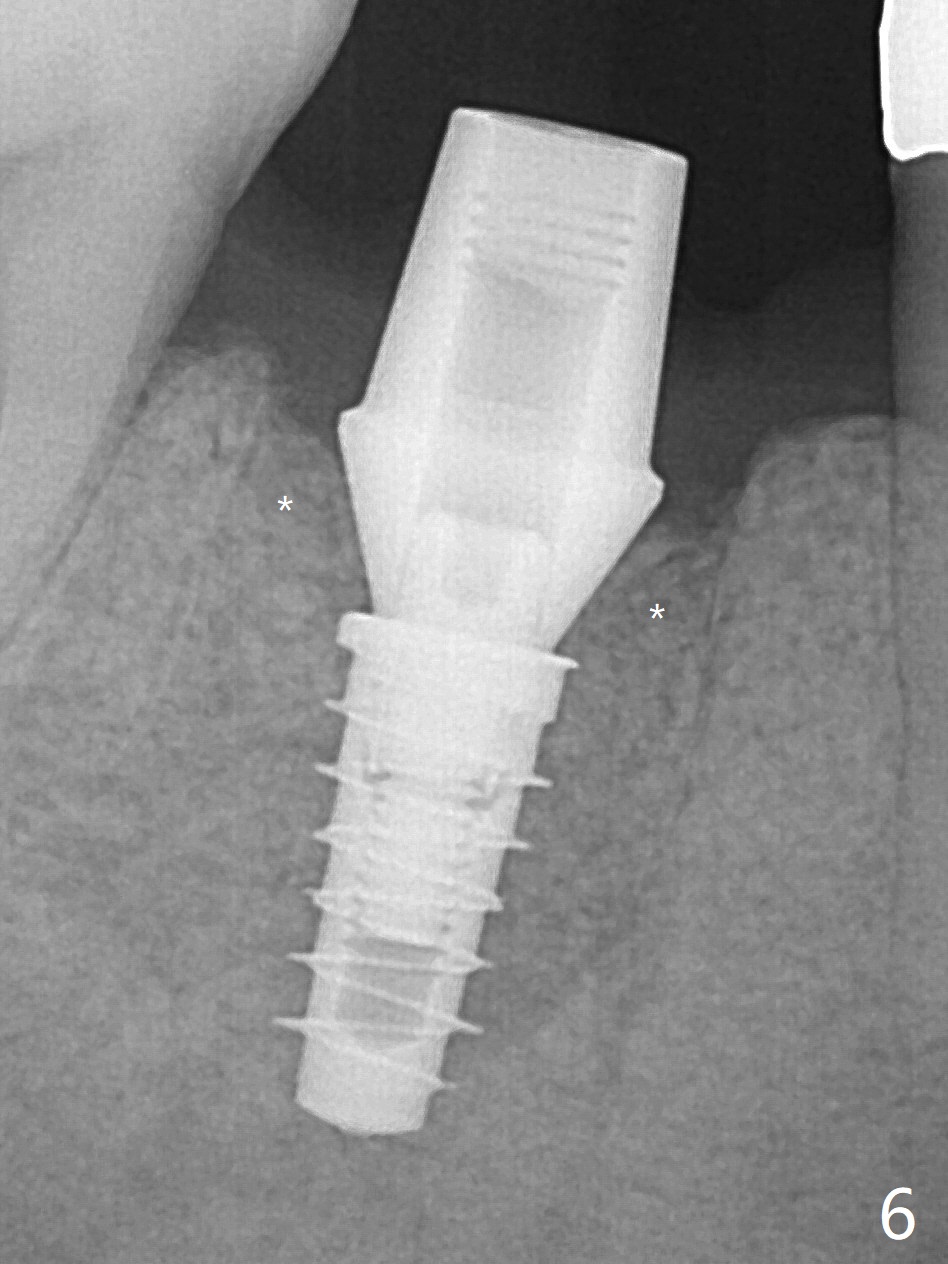

As planned, the crown of the tooth #30 with lingual (Fig.1 L) caries is removed and flattened with surgical handpiece so that the guide is able to be seated without interference. The osteotomy by 10.5 mm offset bone trimmer is lingual (Fig.2 white circle; due to in part the lingual caries and in part design error); in order to let the osteotomy to bounce back buccal, the part of the buccal roots are removed by surgical bur (arrows). The initial osteotomy by 2.2 mm drill is in the middle of the septum (Fig.3). After the last drill (3.5x11.5), the remaining roots are easily removed with proximators; a 4x11 mm dummy implant is placed with low stability and supracrestal lingual (Fig.4). Therefore a 4.5x9 mm final implant is placed with low torque. Following 4x11.5 mm drill, the torque increases to 20 Ncm. With insertion of healing screw, sticky bone (Fig.4 *: .5-1 mm cortical/cancellous allograft) is heavily packed around the implant (arrow), which apparently allows removal of the healing screw and placement of a 6x5.7(3) mm pair abutment without loosening the underlying implant. More bone graft is placed (Fig.6), followed by 2 pieces of PRF membranes. Although the implant is slightly buccally placed (Fig.7, due to over-removal of the buccal root, Fig.2 arrows), it is placed in the septum (Fig.8 S). To further compensate for the low implant stability, setting acrylic is applied in the edentulous area, particularly into the undercuts of the neighboring teeth (Fig.9 *) and around the abutment. The lingual margin of the acrylic dressing is extended (Fig.10 arrow) to cover the soft tissue defect associated with the lingual caries. As compared to the design (4x10 mm, Fig.11), the implant (4.5x9 mm, Fig.12) is placed buccal and ~ 2 mm deeper, reducing the chance of periimplantitis. The acrylic dressing is in place, but has mobility. The gingiva is healthy 2 weeks postop. The dressing is removed 1 month postop; the socket heals around the abutment buccal (Fig.13) and lingual (Fig.14). In spite of the immediate provisional, the abutment margin is substantially subgingival mesial 4 months postop, extremely difficult to take impression. A smaller diameter and longer cuff abutment is placed (Fig.15). The lingual gingiva heals normal 5 months postop, immediately before cementation (Fig.16).